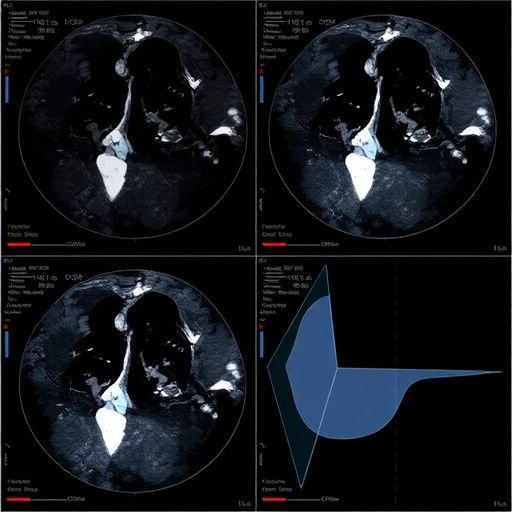

Central to this innovation is the application of ResNet, a deep learning architecture renowned for its ability to extract intricate features from complex image data. The team meticulously analyzed ultrasound images focusing on both the intratumoral region—the core of the tumor—and the peritumoral area, which encompasses the tissue surrounding the tumor. This dual-region approach acknowledges the tumor microenvironment’s role in cancer progression and therapeutic resistance, a factor often overlooked in conventional imaging analyses.

To elevate predictive accuracy, the researchers implemented stacking fusion technology. This technique synergistically combines models trained on different regions of interest (ROIs) within the ultrasound data—specifically, the intratumoral area and concentric peritumoral zones of 3 mm, 5 mm, and 10 mm radii. Such stacking fusion amalgamates distinct predictive signals, resulting in a robust model that outperforms single-region analyses individually.

Technologically, this research exemplifies the power of integrating advanced deep learning frameworks with medical imaging to decipher complex biological signals. The use of ultrasound, a non-invasive, widely accessible imaging modality, further underscores the clinical relevance and feasibility of this approach. Unlike more expensive or less available imaging techniques like MRI or PET, ultrasound can be repeatedly used with minimal risk, supporting dynamic monitoring during NAC.